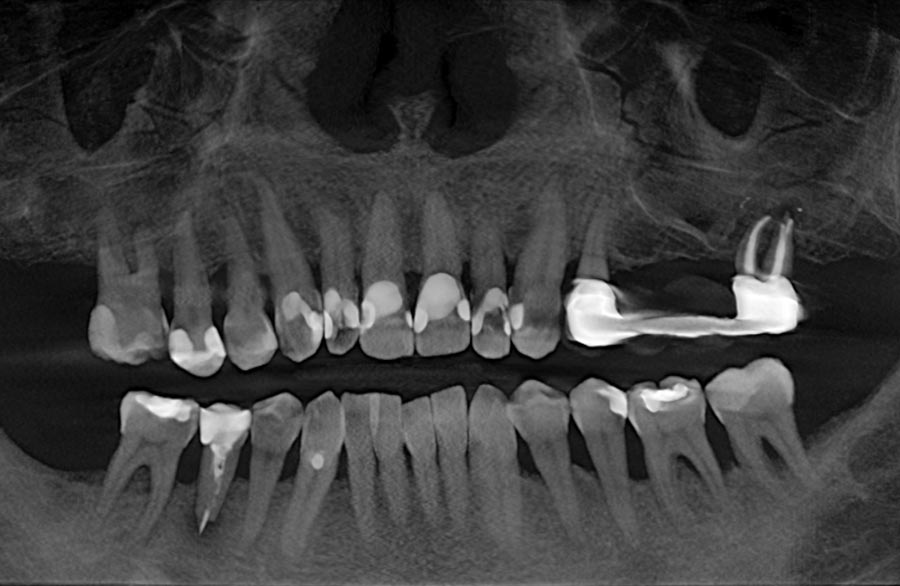

der obige Fall röntgenologisch vorher

Vorher: der obige Fall röntgenologisch vorher

man kann die Keramik-Implantate und den erfolgreichen Knochenaufbau im Unterkiefer, aber auch in beiden Kieferhöhlen (offener Sinuslift) sehr gut erkennen; auch den perfekten Sitz aller vollkeramischen Kronen

Nachher: man kann die Keramik-Implantate und den erfolgreichen Knochenaufbau im Unterkiefer, aber auch in beiden Kieferhöhlen (offener Sinuslift) sehr gut erkennen; auch den perfekten Sitz aller vollkeramischen Kronen